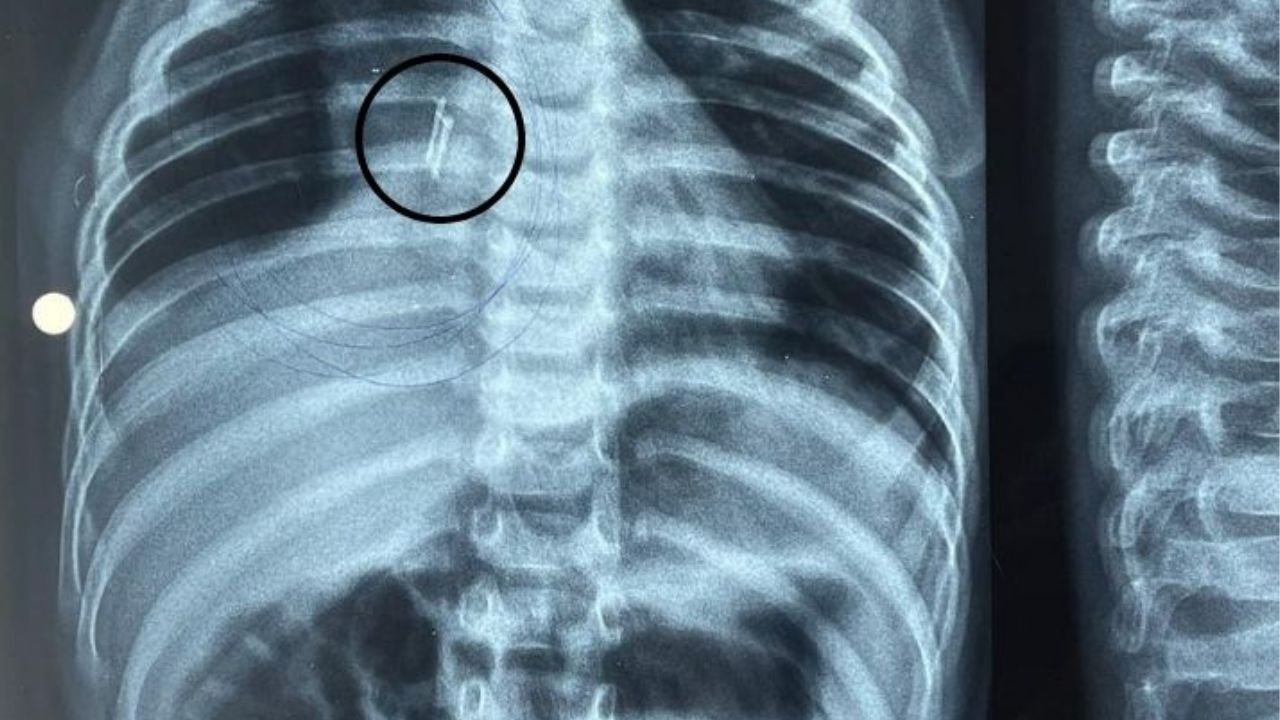

ಅಹಮದಾಬಾದ್: ನಿರಂತರ ಉಸಿರಾಟದ ತೊಂದರೆಯಿಂದ ಬಳಲುತ್ತಿದ್ದ ಒಂದು ವರ್ಷದ ಬಾಲಕನ ಶ್ವಾಸನಾಳದಲ್ಲಿ ಎಲ್ಇಡಿ ಬಲ್ಬ್ (LED bulb in child’s windpipe) ಸಿಲುಕಿಕೊಂಡಿದ್ದ ಆಘಾತಕಾರಿ ಘಟನೆ ನಡೆದಿದೆ. ಇದನ್ನು ಕಂಡು ವೈದ್ಯರೇ ದಂಗಾಗಿ ಹೋಗಿದ್ದಾರೆ. ಗುಜರಾತ್ನ (Gujarat) ವಡೋದರಾ ಜಿಲ್ಲೆಯಲ್ಲಿ ಈ ಘಟನೆ ನಡೆದಿದೆ.

ಮಗುವಿನ ಕುಟುಂಬಸ್ಥರು ಹಲವಾರು ಖಾಸಗಿ ಆಸ್ಪತ್ರೆಗಳಲ್ಲಿ ಭೇಟಿ ನೀಡಿದ್ದಾರೆ. ಆ ಮಗು ತೀವ್ರ ಜ್ವರ ಮತ್ತು ದೀರ್ಘಕಾಲದಿಂದ ಕೆಮ್ಮಿನಿಂದ ಬಳಲುತ್ತಲೇ ಇತ್ತು. ವಾರಗಳ ಕಾಲ ಚಿಕಿತ್ಸೆ ಫಲಕಾರಿಯಾಗದ ನಂತರ, ವೈದ್ಯರು ಆರಂಭದಲ್ಲಿ ಸಾಮಾನ್ಯ ಉಸಿರಾಟದ ಸೋಂಕು ಆಗಿರಬಹುದು ಎಂದು ಊಹಿಸಿದ್ದರು. ಆದರೆ, ಅದು ಶ್ವಾಸನಾಳದಲ್ಲಿ ಸಿಲುಕಿಕೊಂಡಿದ್ದ ಸಣ್ಣ ಎಲ್ಇಡಿ ಬಲ್ಬ್ ಎಂಬುದನ್ನು ಬಳಿಕ ಪತ್ತೆಮಾಡಿದರು.

ವಡೋದರಾದ ಮಲ್ಸರ್ ಗ್ರಾಮದಲ್ಲಿ ಈ ಘಟನೆ ನಡೆದಿದೆ. ಖಾಸಗಿ ಆಸ್ಪತ್ರೆಗಳ ವೈದ್ಯರು ಆರಂಭದಲ್ಲಿ ಬಾಲಕನಿಗೆ ನ್ಯುಮೋನಿಯಾಗೆ ಚಿಕಿತ್ಸೆ ನೀಡಿದರು. ಆದರೆ ಅವನ ಸ್ಥಿತಿ ಸುಧಾರಿಸದಿದ್ದಾಗ, ಕುಟುಂಬವು ಅವನನ್ನು ಗೋತ್ರಿಯಲ್ಲಿರುವ ಸರ್ಕಾರಿ ಆಸ್ಪತ್ರೆಗೆ ಕರೆದೊಯ್ದಿತು.

ಆಸ್ಪತ್ರೆಯ ಇಎನ್ಟಿ ವಿಭಾಗದ ವೈದ್ಯರು ಕೂಲಂಕಷ ಪರೀಕ್ಷೆ ನಡೆಸಿದಾಗ ಬಾಲಕನ ಶ್ವಾಸನಾಳದಲ್ಲಿ ಅಪರಿಚಿತ ವಸ್ತುವಿನಿಂದಾಗಿ ಬಾಲಕ ಬಳಲುತ್ತಿದ್ದಾನೆ ಎಂದು ಕಂಡುಬಂದಿದೆ. ವೈದ್ಯರು ಬ್ರಾಂಕೋಸ್ಕೋಪಿ ವಿಧಾನವನ್ನು ನಡೆಸಿ ಶ್ವಾಸನಾಳದಲ್ಲಿ ಸಿಲುಕಿಕೊಂಡಿದ್ದ ಎಲ್ಇಡಿ ಬಲ್ಬ್ ಅನ್ನು ಹೊರತೆಗೆದರು.

ಪರೀಕ್ಷೆಯ ಸಮಯದಲ್ಲಿ ಶ್ವಾಸನಾಳದಲ್ಲಿ ಸಮಸ್ಯೆ ಇರುವುದು ಕಂಡುಬಂದಿದೆ. ಎಕ್ಸ್-ರೇ ಮಾಡಿದಾಗ ಏನೋ ವಸ್ತುವಿದೆ ಎಂಬುದು ಗೋಚರಿಸಿತು. ಹೀಗಾಗಿ ಬ್ರಾಂಕೋಸ್ಕೋಪ್ ಮೂಲಕ ಪರೀಕ್ಷೆ ಮಾಡಲಾಯಿತು. ಈ ವೇಳೆ ಸಣ್ಣ ಲೋಹದ ತುಂಡುವಿನಂತೆ ಕಾಣುವ ವಸ್ತು ಗಮನಕ್ಕೆ ಬಂತು ಎಂದು ಗೋತ್ರಿಯ ಜಿಎಂಇಆರ್ಎಸ್ ಆಸ್ಪತ್ರೆಯ ಇಎನ್ಟಿ ಮುಖ್ಯಸ್ಥ ಡಾ. ಹಿರೇನ್ ಸೋನಿ ಹೇಳಿದ್ದಾರೆ.

ಮಗು ಒಂದೂವರೆ ತಿಂಗಳಿನಿಂದ ಅನಾರೋಗ್ಯದಿಂದ ಬಳಲುತ್ತಿದ್ದ ಕಾರಣ, ಅದರ ಮೇಲೆ ಚರ್ಮ ಬೆಳೆದಿತ್ತು. ಆಧುನಿಕ ಉಪಕರಣಗಳ ಸಹಾಯದಿಂದ, ಒಂದು ಸೆಂಟಿಮೀಟರ್ನ ಬಲ್ಬ್ ಅನ್ನು ತೆಗೆದುಹಾಕಲು ನಮಗೆ ಸಾಧ್ಯವಾಯಿತು. ಮಗುವಿನ ಶ್ವಾಸನಾಳದಲ್ಲಿ ಎಲ್ಇಡಿ ಬಲ್ಬ್ ಸಿಕ್ಕಿಹಾಕಿಕೊಂಡಿತ್ತು. ಈಗ, ಬಲ್ಬ್ ಅನ್ನು ಹೊರತೆಗೆದ ನಂತರ, ಮಗು ಆರೋಗ್ಯವಾಗಿದೆ ಎಂದು ಡಾ. ಸೋನಿ ಹೇಳಿದರು.